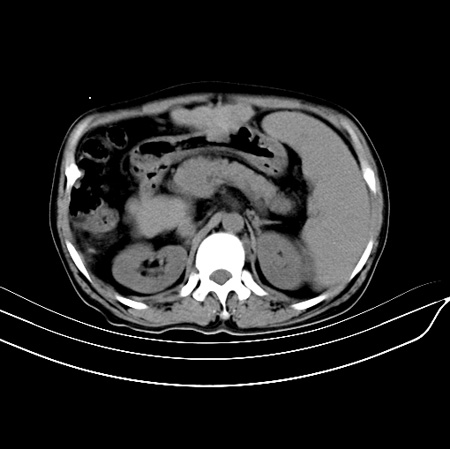

以下是引用江尾海头在2007-9-7 19:01:00的发言:[br]肝叶比例失调,肝边缘高低不平,尾状叶增大,肝裂增宽。肝右叶见较大密度减低影,边缘欠清。脾脏明显增大,胃底及奇静脉半奇静脉曲张。胆囊未见明显显示。 考虑:1、肝癌。2、肝硬化伴脾大静脉曲张。

以下是引用zhangxu5888在2007-9-7 22:31:00的发言:[br]1、肝硬化,食管 胃底及奇静脉半奇静脉曲张;2、脾脏肿大; 3、肝右叶的病灶呈锲性改变,内可见条片状钙化,边界清晰,密度明显低于周围正常肝组织,我觉得肝癌可能性不是很大, 同意楼上观点,有可能是栓塞,建议增强.